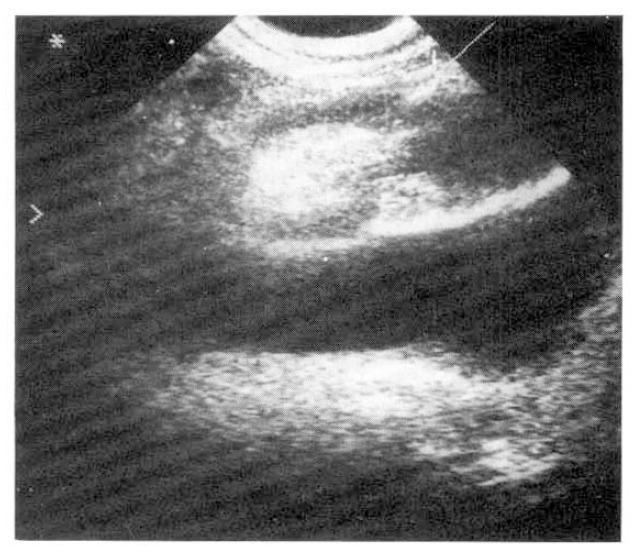

A 52-year-old woman was presented with intermittent abdominal pain and vomiting for 10 days. Abdominal CT scan disclosed a dilated small bowel loop with a round solid mass in the right anterior supravesical space. The clinical impression was intussusception caused by small bowel tumor. She underwent an exploratory laparotomy. The macroscopic and microscopic findings confirmed an inflammatory fibroid polyp of jejunum causing intussusception. To the best of our knowledge, this was the 5th reported case of such a presentation in English medical literature.

一名52岁女性出现间歇性腹痛和呕吐10天。腹部CT扫描显示一个扩张的小肠袢,在膀胱上间隙右前方有一个圆形实性肿块。临床诊断为小肠肿瘤引起的肠套叠。她接受了剖腹探查术。大体和显微镜检查结果证实为空肠炎性纤维性息肉导致肠套叠。据我们所知,这是英文医学文献中报道的第5例此类病例。